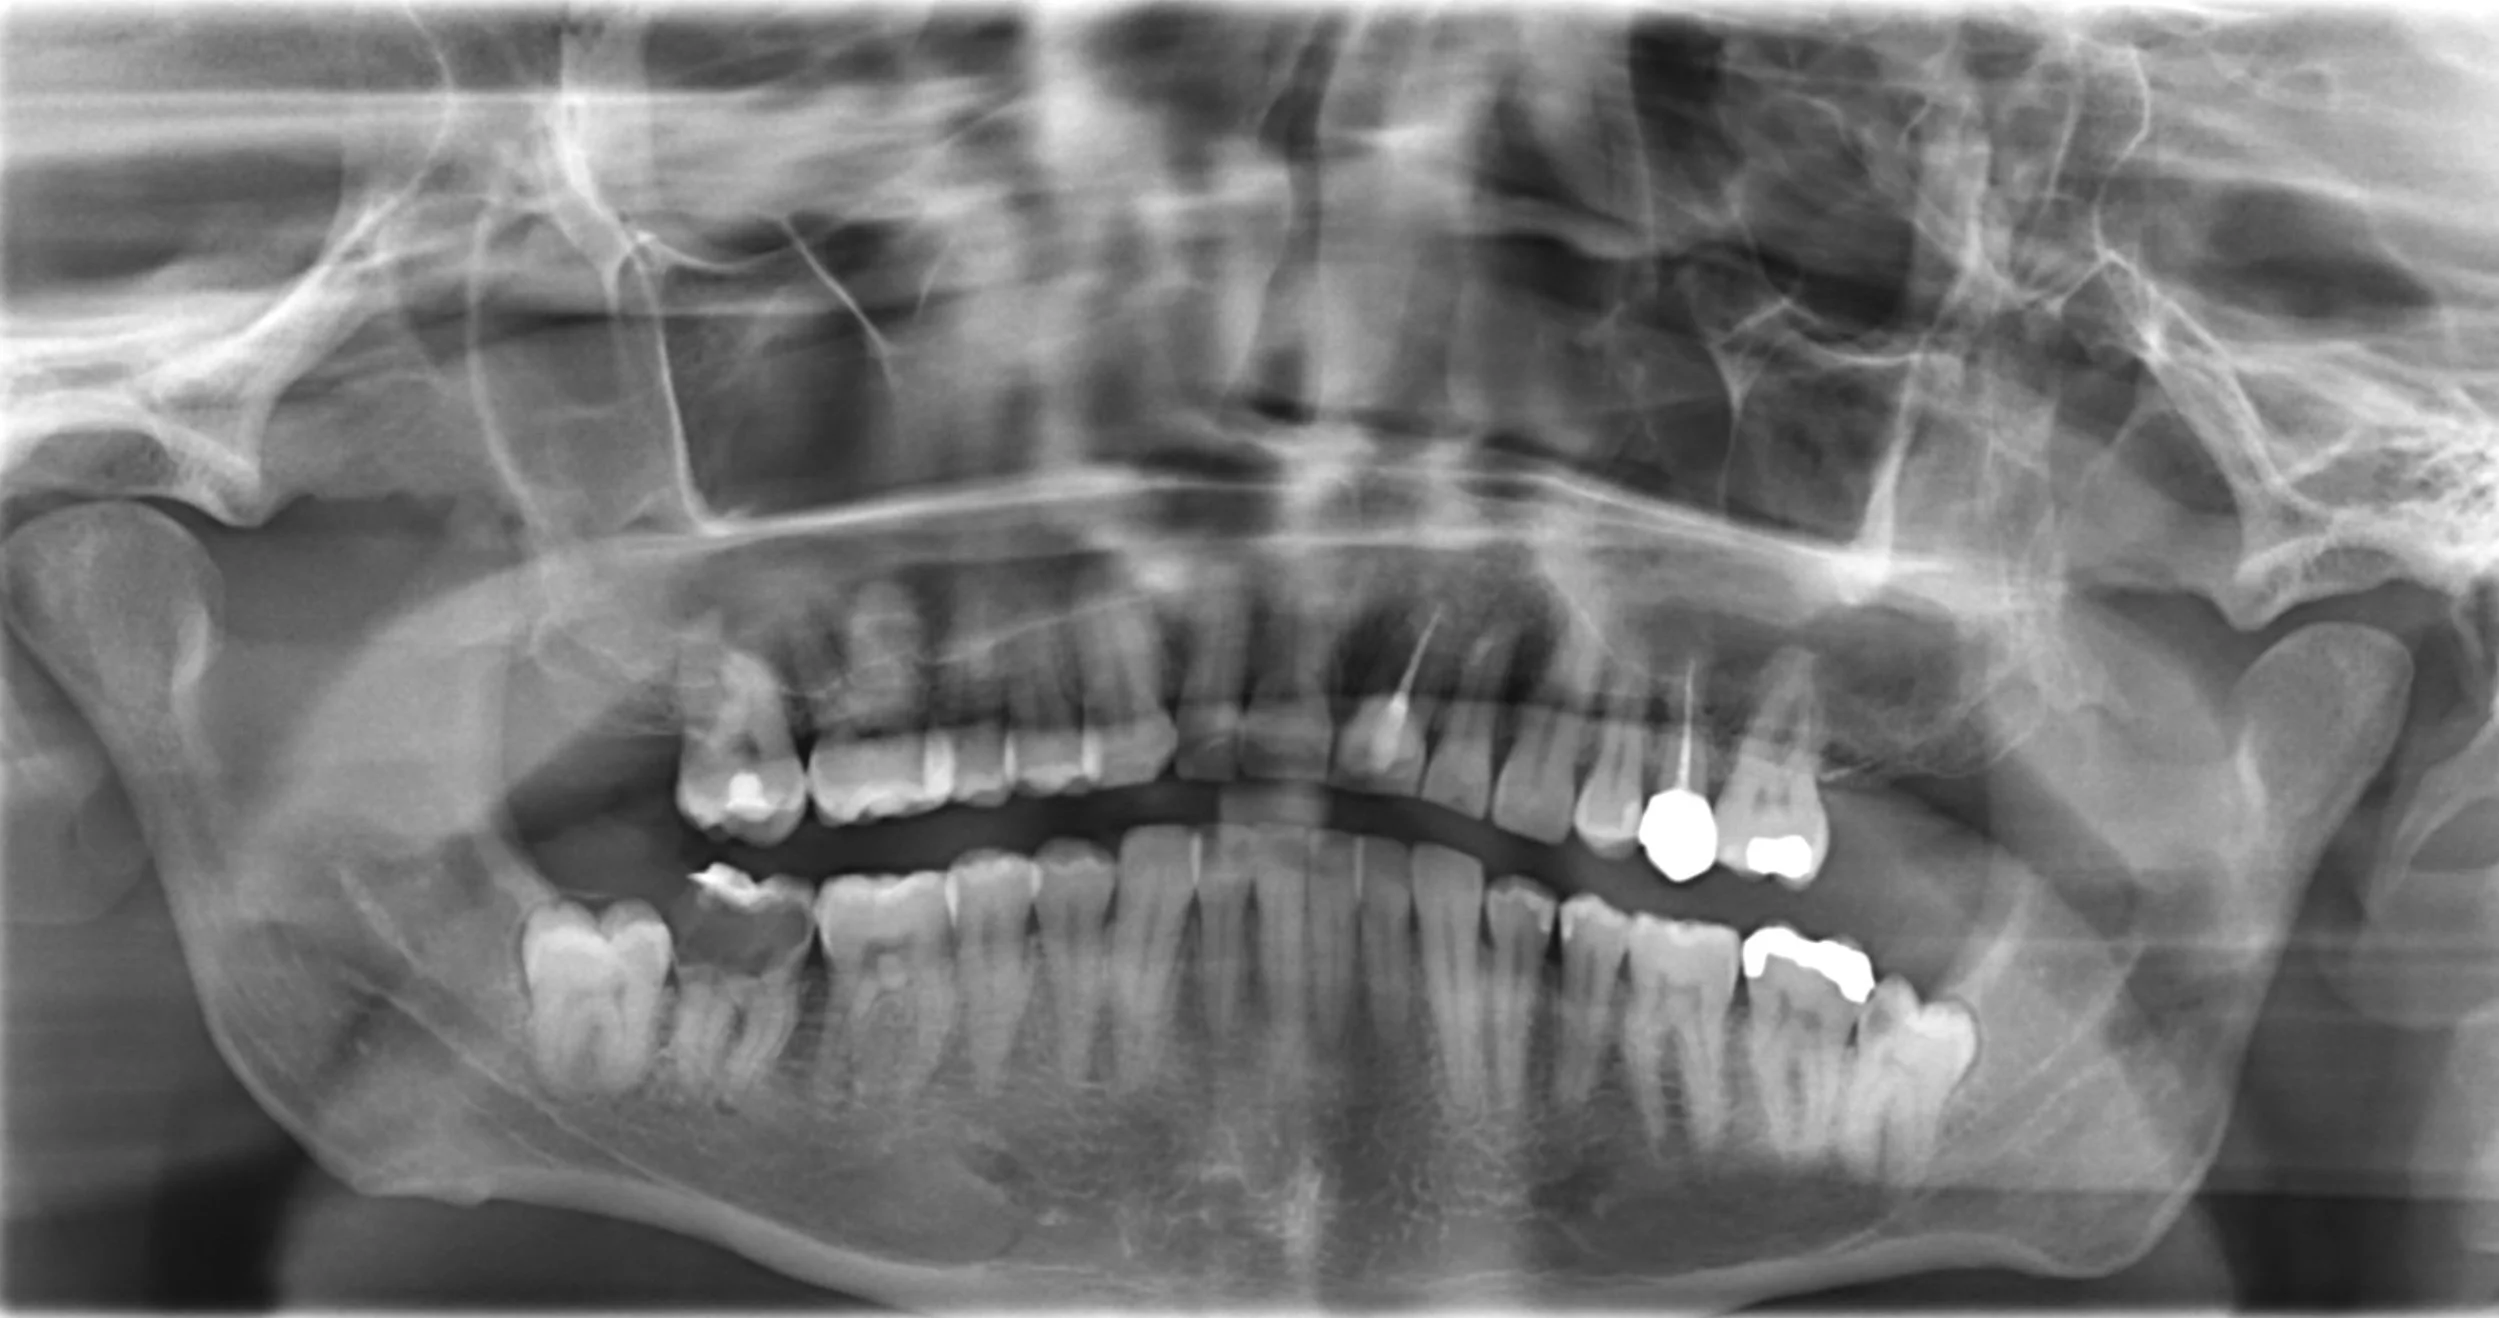

During your initial consultation, we will take a CT scan, a 4D image that allows our specialist to see if you are a fit candidate to receive dental implants. This decision heavily relies on your existing bone level and placement location. This image also defines the size and amount of dental implants to be placed and if any bone graft and membrane will be necessary. In addition, he will use this image to place the implant digitally, allowing visibility to increase predictability and safety prior to surgery. Dr. Ribeiro will work closely with his restorative associates to give you the best path to your new tooth/teeth. Depending on how many teeth you are missing, there are various types of implant-held restorations for your needs.

You are most likely in pain and need to remove a tooth or teeth that no longer have a good prognosis. During your initial consultation, we will take a CT scan, which is a 4D image that allows our specialist to see which teeth need to be extracted and if you are a fit candidate to receive dental implants. This decision heavily relies on your existing bone level, considering the bone you will lose at the time of extraction and the placement location. This image also defines the size and amount of dental implants to be placed.  In addition, he will use this image to place the implant digitally, allowing visibility to increase predictability and safety prior to surgery. Dr. Ribeiro will work closely with his restorative associates to give you the best path forward to your new tooth/teeth. Depending on how many teeth you will need to replace, there are various types of implant held restorations.